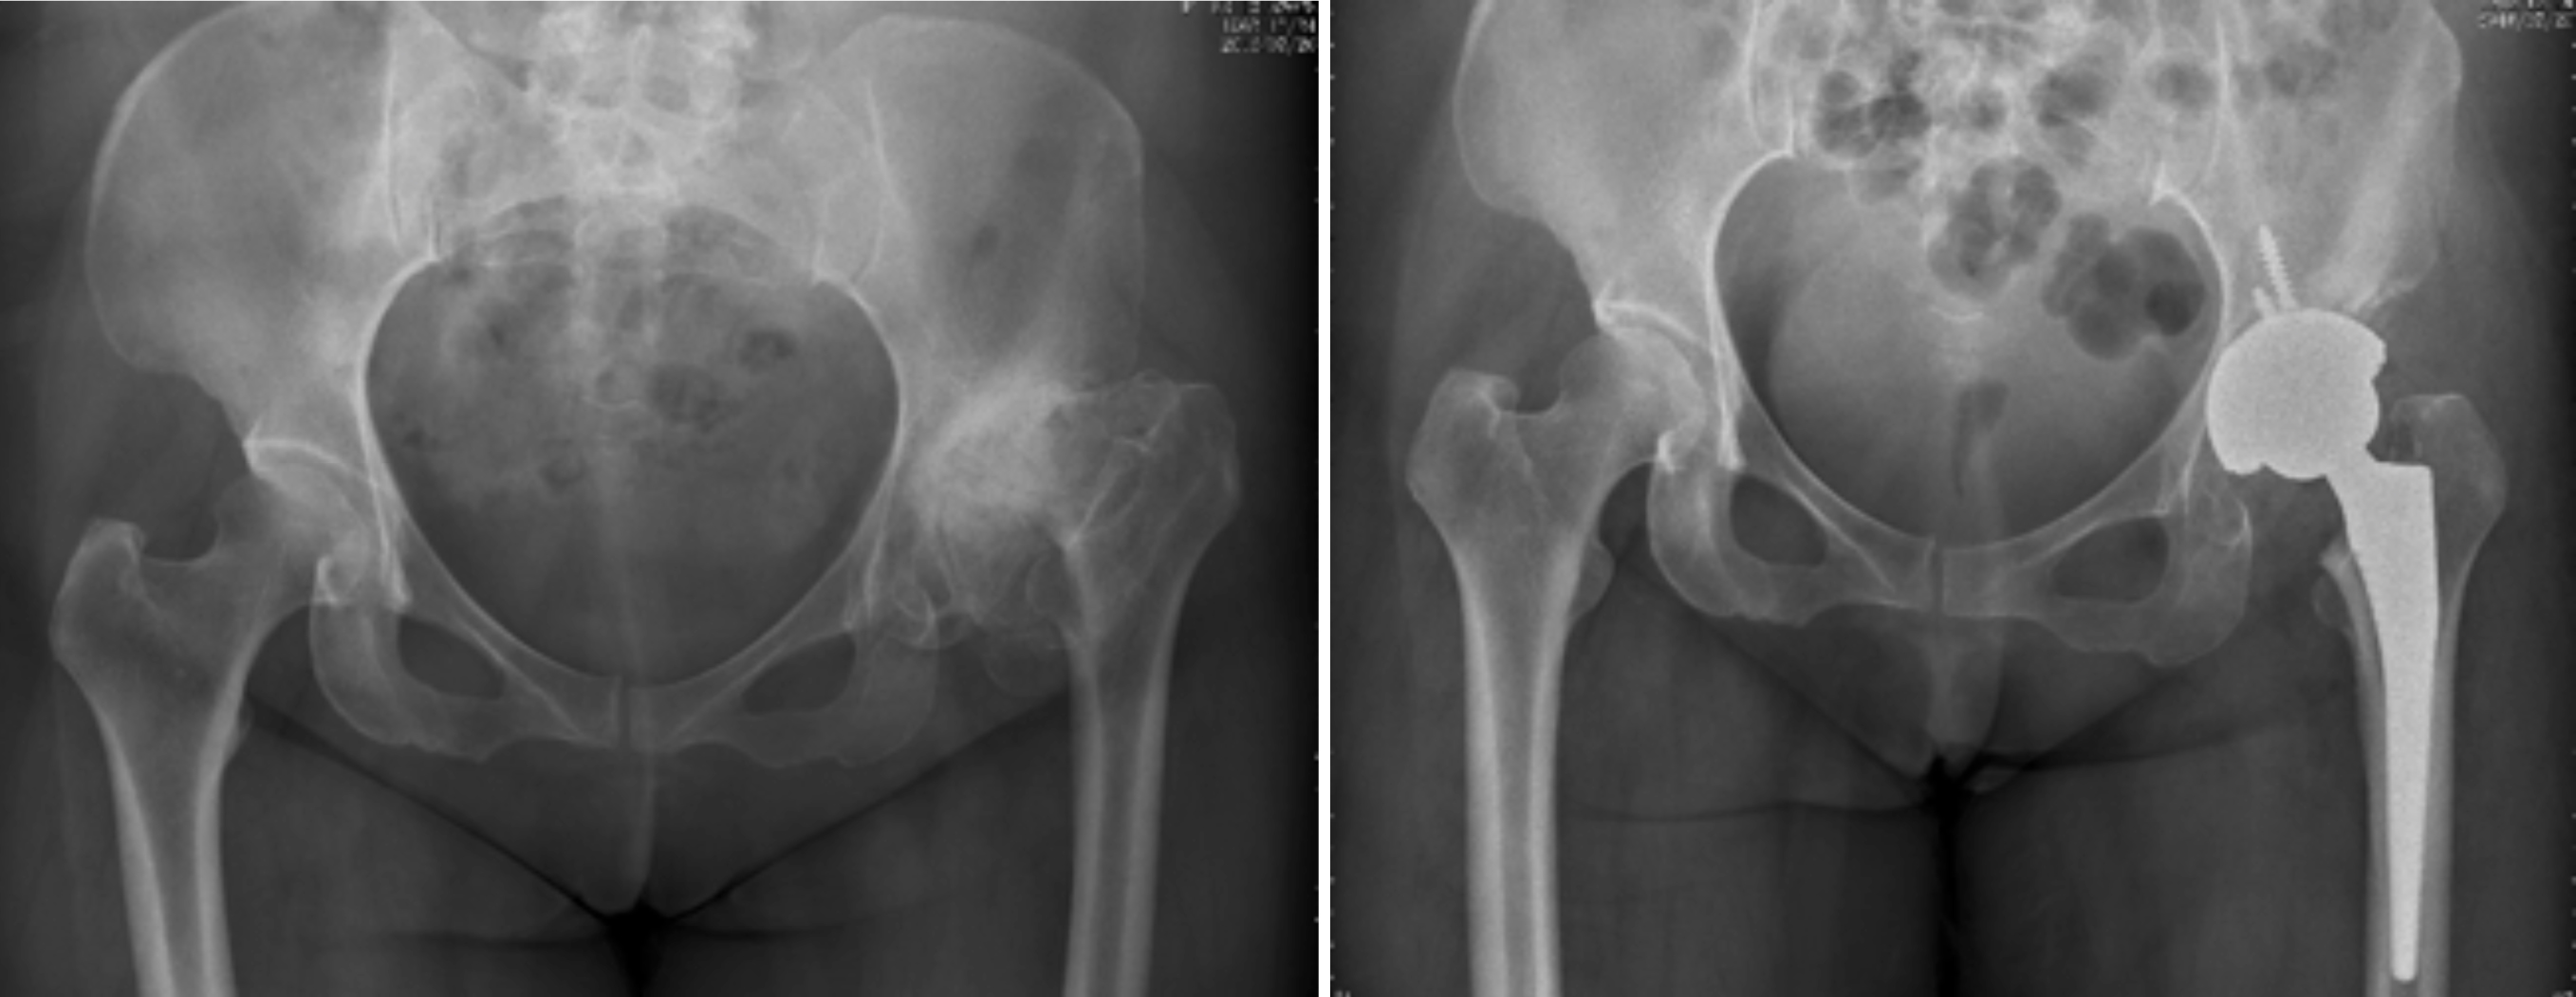

一、人工关节置换 各种晚期骨关节病的关节置换手术治疗是北京清华长庚医院关节外科中心的一大特色,包括股骨头坏死、髋膝骨关节炎、类风湿关节炎、强直性脊柱炎、髋关节发育不良、关节强直、超过80岁的超高龄股骨颈骨折患者的关节置换手术等,我中心在人工关节初次置换及翻修上作了大量工作,置换的难度和手术效果方面已达到国际先进水平,导航下全膝关节置换术:大大提高膝关节置换手术的精确度。

股骨头缺血性坏死

髋关节发育不良

强直性脊柱炎双髋强直

股骨颈骨折